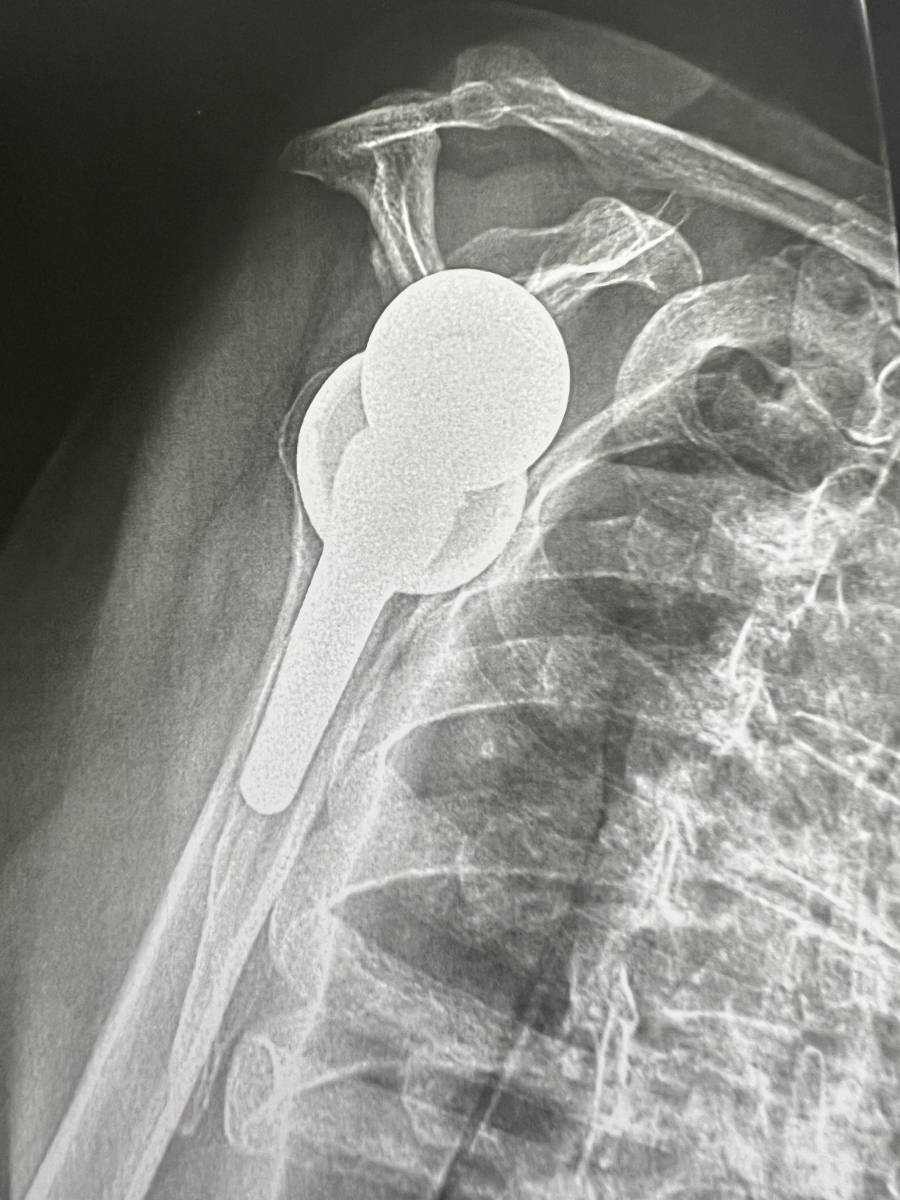

Chirurgie de l'Épaule par Prothèse : Comprendre l'Intervention et ses bénéfices

La Chirurgie de l'Épaule par Prothèse : Comprendre l'Intervention et ses bénéfices

Prothèse d’épaule : traitement efficace de l’arthrose avancée pour soulager les douleurs et retrouver une mobilité fonctionnelle.